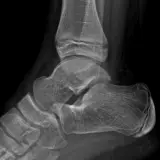

Over 2,100 interactive radiology cases, curated by radiologists for your level of training. Scroll, window, and view cases full screen โ€” just like on PACS. Click linked findings in each writeup to jump straight to them on the image. Cases include sample reports, a focused discussion section, original illustrations, and videos.

PACS์—์„œ ๊ธฐ๋Œ€ํ•  ์ˆ˜ ์žˆ๋Š” ๋ชจ๋“  ๋„๊ตฌ๋ฅผ ๊ฐ–์ถ˜ ์™„์ „ํ•œ ์ธํ„ฐ๋ž™ํ‹ฐ๋ธŒ ์ฆ๋ก€ — ์Šคํฌ๋กค, ์œˆ๋„์šฐ ์กฐ์ ˆ, ํ™•๋Œ€/์ถ•์†Œ, ํŒจ๋‹, ๊ณ„์ธก, ROI, ์ „์ฒด ํ™”๋ฉด ๋ชจ๋“œ๊นŒ์ง€ ์ง€์›ํ•ฉ๋‹ˆ๋‹ค.

์ฃผ์š” ์†Œ๊ฒฌ์„ ์ฆ๋ก€์— ์ง์ ‘ ํ‘œ์‹œํ•˜๋Š” ํ’๋ถ€ํ•œ ์ฃผ์„์ด ํฌํ•จ๋˜์–ด ์žˆ์Šต๋‹ˆ๋‹ค. ์ฆ๋ก€ ์„ค๋ช…์˜ ์—ฐ๊ฒฐ๋œ ์†Œ๊ฒฌ์„ ํด๋ฆญํ•˜๋ฉด ์Šค์บ” ๋‚ด ์ •ํ™•ํ•œ ์œ„์น˜๋กœ ๋ฐ”๋กœ ์ด๋™ํ•ฉ๋‹ˆ๋‹ค.

์–ด๋ ค์šด ์ฆ๋ก€๋ฅผ ์ •ํ™•ํžˆ ํŒ๋…ํ•˜๋Š” ๋น„๊ฒฐ์€ ๋Œ€๊ฐœ ์œ ์‚ฌํ•œ ์ฆ๋ก€๋ฅผ ์ด์ „์— ๋ณธ ์ ์ด ์žˆ๋Š”์ง€์— ๋‹ฌ๋ ค ์žˆ์Šต๋‹ˆ๋‹ค. ํฌ๊ด„์ ์ธ ์ง„๋‹จ ๋ชฉ๋ก์„ ์•„์šฐ๋ฅด๋Š” 1,900๊ฐœ ์ด์ƒ์˜ ์—„์„ ๋œ ์ฆ๋ก€๋กœ ์—ฐ์Šตํ•˜์„ธ์š”.